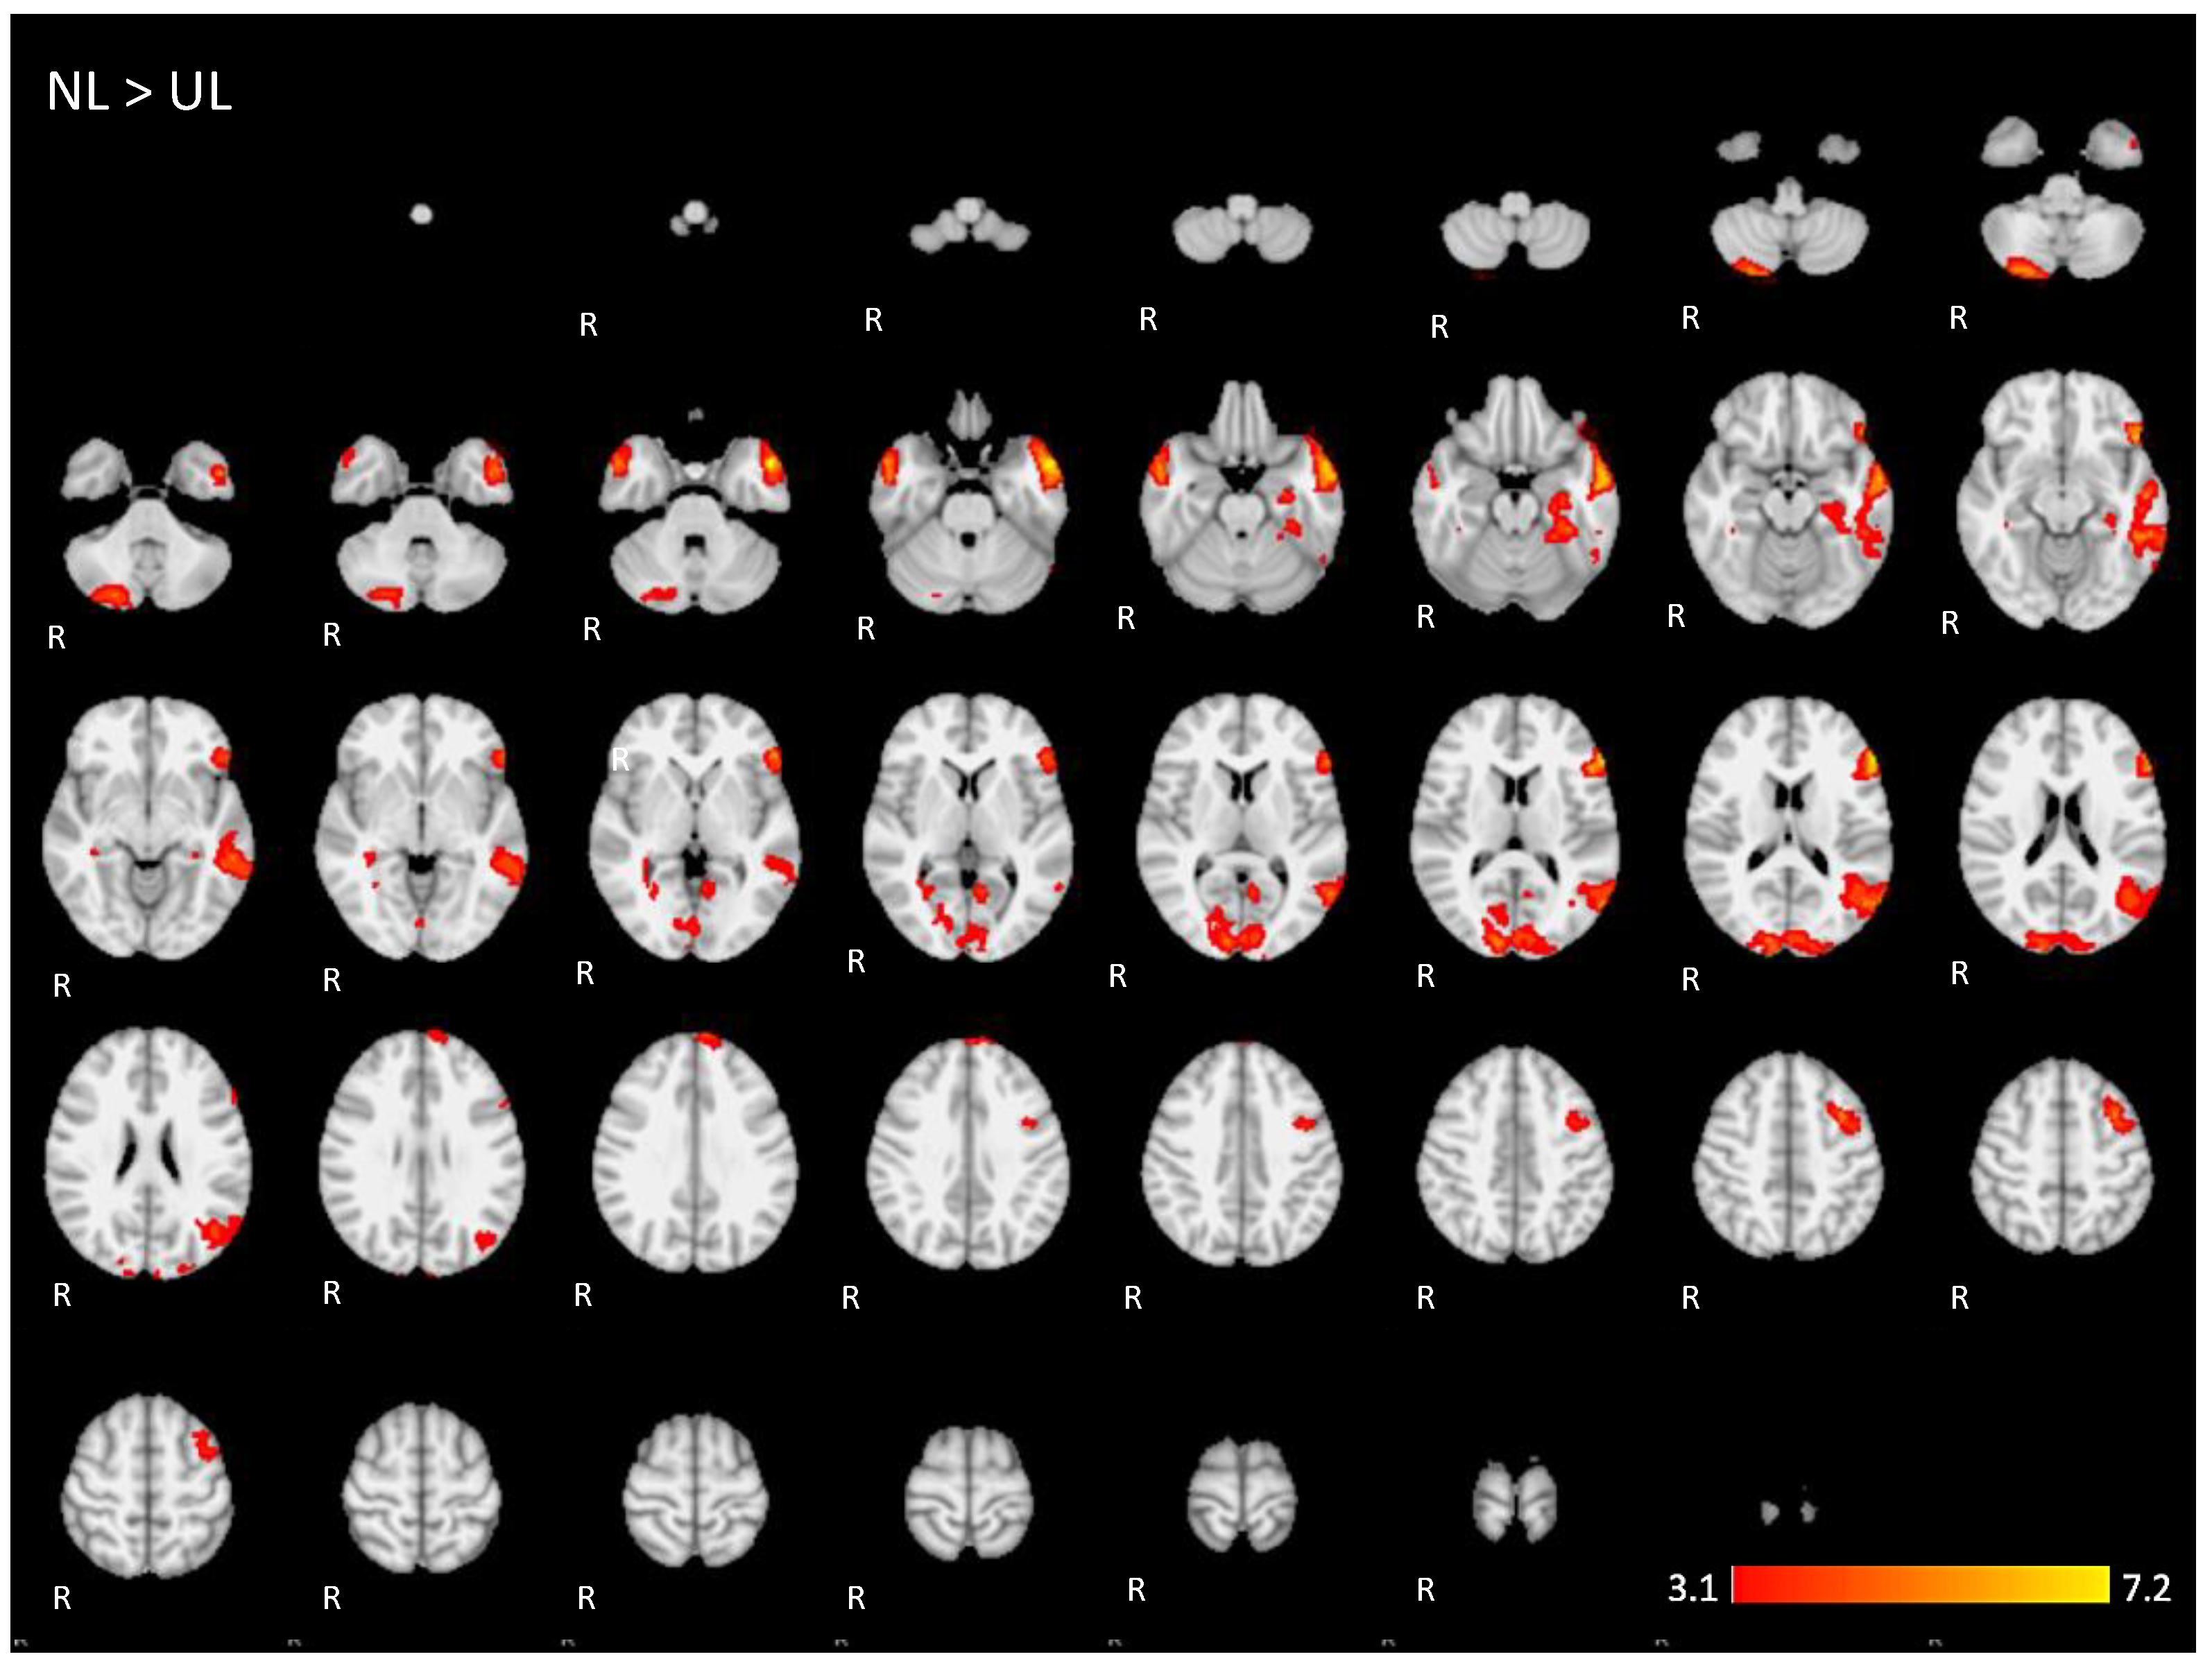

When directly comparing both active conditions, in the contrast (NL > UL), the ventral network was especially enhanced with significant left hemisphere activations covering regions from the temporo-occipital junction into the middle temporal gyrus and on into the temporal pole and the inferior frontal gyrus, mainly in the pars triangularis. The right temporal pole was also activated. Additionally, the bilateral occipital lobe, cuneus, and the posterior lobe of right cerebellum were also activated (images of third line of Figure 5 and Appendix A Figure A3).

The brain activation maps are shown in Figure 5 using the main slices of the 2D fMRI maps for the active conditions NL and UL and for the contrasts NL > UL and UL > NL. The 2D fMRI maps of all brain slices for both active conditions (NL, UL) and for both contrasts (NL > UL and UL > NL) are in Appendix A (Figure A1, Figure A2, Figure A3 and Figure A4, respectively).

Figure A3.

Two-dimensional fMRI map of auditory attention task (n = 25) for the contrast native language (NL) condition higher than unknown language (UL) condition. (Red–yellow scale indicates the z-score > 3.1; p < 0.05).